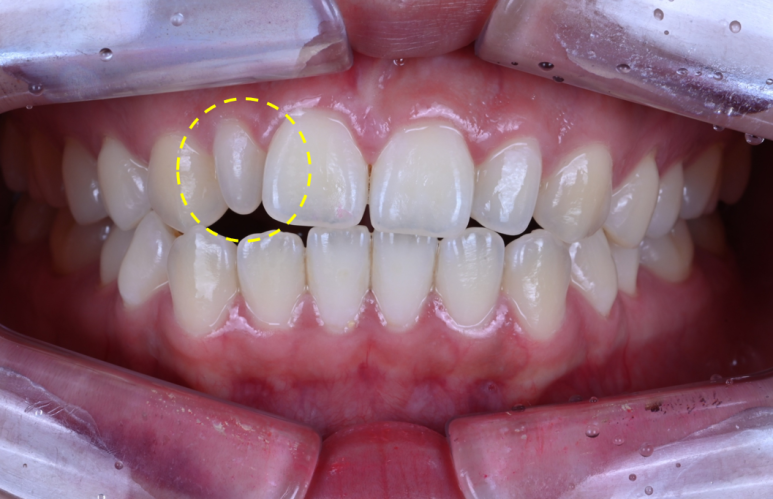

바로 이 녀석입니다!

왜소치. 모양도 참 안예뻐요... 뾰족하고...

왜소치의 아주 특징적인 모습을 보여주고 있는 분이었어요.

왜소치가 있으면, 작은 치아 폭 때문에 은근히 다른 치아 사이에도 틈이 남게 됩니다.

보시면 대문니 사이에 약간의 틈이 있죠? 이것도 함께 해결하고 싶어하셨어요.